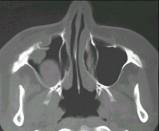

问题 女性,50岁,右鼻塞、脓涕3个月,CT、MRI检查如图所示,请选择正确的答案()

选项 A.右侧上颌窦黏液囊肿 B.右侧上颌窦粘膜下囊肿 C.右侧上颌窦积液 D.右侧上颌窦黏液腺瘤 E.右侧上颌窦腺样囊性癌

答案 E